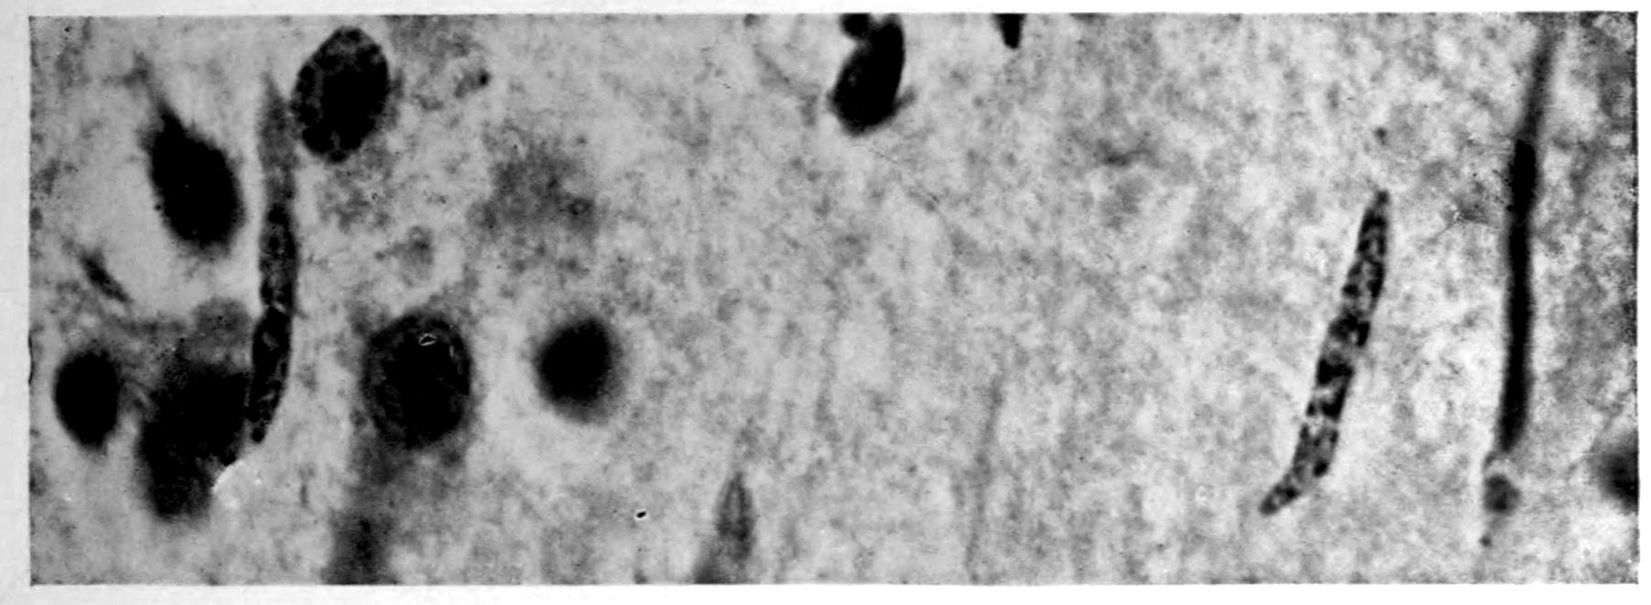

Apparent new formation of small blood vessel. Photographed by Dr. A. M. Barrett.

Rod cells (Stäbchenzellen) in paretic neurosyphilis. Photographed by Dr. A. M. Barrett.

Granular ependymitis—microscopic appearance of a marked example of “sanding” of ventricle.

41Characteristic and constant in paretic neurosyphilis is the Plasmocytosis and Lymphocytosis, Perivascular in distribution about small cortical vessels. There is also a characteristic (though characteristically less prominent) Plasmocytosis and Lymphocytosis, Meningeal in distribution. The pleocytosis of the spinal fluid, almost constant though variable in amount in life, is an indicator of the meningeal picture and less directly of the parenchymatous picture.

Granular Ependymitis (“sanding” of ventricle floors) is characteristic and may be regarded as part of the parenchymatous picture. This ependymitis is an indicator how chemical changes could be readily produced at least in the ventricular fluids, since the limiting membranes of the nerve tissue are here subject to multiple breaks. The “sanding” is a neuroglia reaction to these multiple small breaks (Weigert’s explanation).